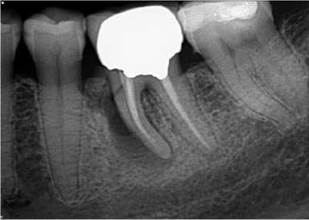

Periapical radiographs are currently the primary tool as the first line for radiographic assessment of the periapical tissues. It is a quick and simple technique to use, and images are relatively easy to interpret. In addition, it has good specificity and high image resolution. The limitations of periapical radiography are the superimposition of overlying anatomy; the 2-dimensional nature of the image being produced; and the geo- metric distortion (Figure 6.1). These factors result in less than ideal sensitivity [93].

Figure 6.1 Geometric distortion. (a) Periapical radiograph of a root treated upper right molar tooth does not reveal anything untoward, (b) however, the change in the bitewing radiograph reveals a deficient crown margin (red arrow).